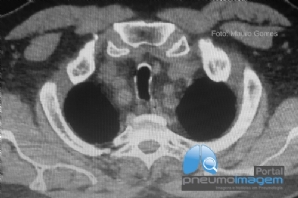

CASO CLÍNICO #53

Paciente do sexo feminino, 74 anos, asmática sob o uso de formoterol 12mcg/budesonida 400mcg – 2x/dia, apresenta-se com dor retroesternal, odinofagia, náuseas e inapetência. O exame endoscópico mostrou essa imagem. Qual o provável diagnóstico? Deixe seus comen...